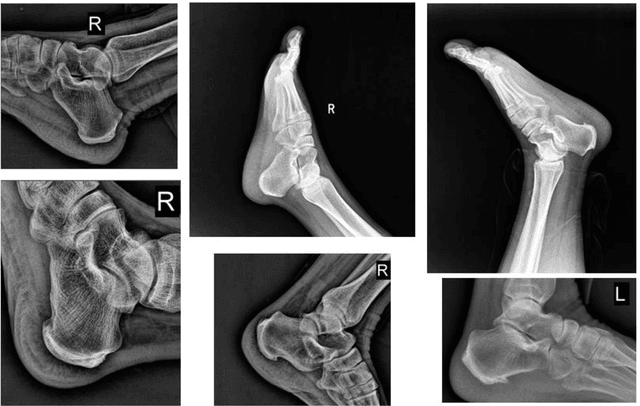

Calcaneus is the largest tarsal bone to withstand the daily stresses of weight bearing. The calcaneal fracture is the most common type in the tarsal bone fractures. After a fracture is suspected, plain radiographs should be taken first. Bohler's Angle (BA) and Critical Angle of Gissane (CAG), measured by four anatomic landmarks in lateral foot radiograph, can aid operative restoration of the fractured calcaneus and fracture diagnosis and assessment. The aim of this study is to develop a system to automatically locate four anatomic landmarks and measure BA and CAG for fracture assessment. To solved the problem of fickle rotation of calcaneus, we proposed a coarse-to-fine Rotation-Invariant Regression-Voting (RIRV) landmark detection method based on Supported Vector Regression (SVR) and Scale Invariant Feature Transform (SIFT) patch descriptor. By implementing a novel normalization approach to convert displacements into coordinates of oriented feature patches, our method is explicit rotation-invariance comparing with traditional regressive method. A multi-stream CNN structure with multi-region input is designed to screen calcaneus fracture. The input ROIs of multi-stream CNN are normalized by detected landmarks to uniform view, orientation and scale. The advantage of our approach is the usage of landmarks using prior knowledge to normalize the inputs of CNN so as to improve the efficiency of CNN. Experiments show that our CNN can accurately identify the fractures with sensitivity of 95.21% and specificity of 95.32%.